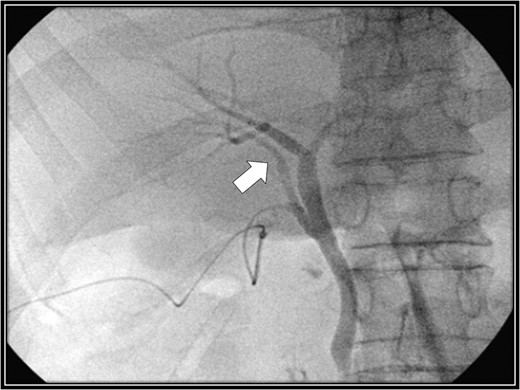

The patient was placed in supine position. Initially, intracorporeal procedures were performed in the laparoscopic view through four trocars (one 12-mm port and three 5-mm ports). We considered using intraoperative cholangiography to explore the right accessory hepatic duct. We incised the serosa by the neck of the gallbladder, used the Rouviere sulcus as a landmark, and peeled off the Calot triangle near the gallbladder. Subsequently, we identified the cystic artery and isolated it. Then we identified the cystic duct, and we inserted a cholangiography tube into it. The intraoperative cholangiography image showed that the right accessory hepatic duct branching from the cystic duct dominated an anterior segment of the right hepatic lobe (Fig. 3). Next, we isolated the cystic duct while preserving the right accessory hepatic duct. We resected the gallbladder. The total operating time was 125 min, and the intraoperative blood loss was minimal. Since the patient's postoperative course was uneventful, he was discharged 4 days later. We performed drip-infusion cholangiography-CT (DIC-CT) 48 days postoperatively. The DIC-CT scan demonstrated that the right accessory hepatic duct was intact, and it dominated an anterior segment of the right hepatic lobe (Fig. 4).

Intraoperative cholangiography image. The right accessory hepatic duct branching from the cystic duct (white arrow) dominates an anterior segment of the right hepatic lobe.